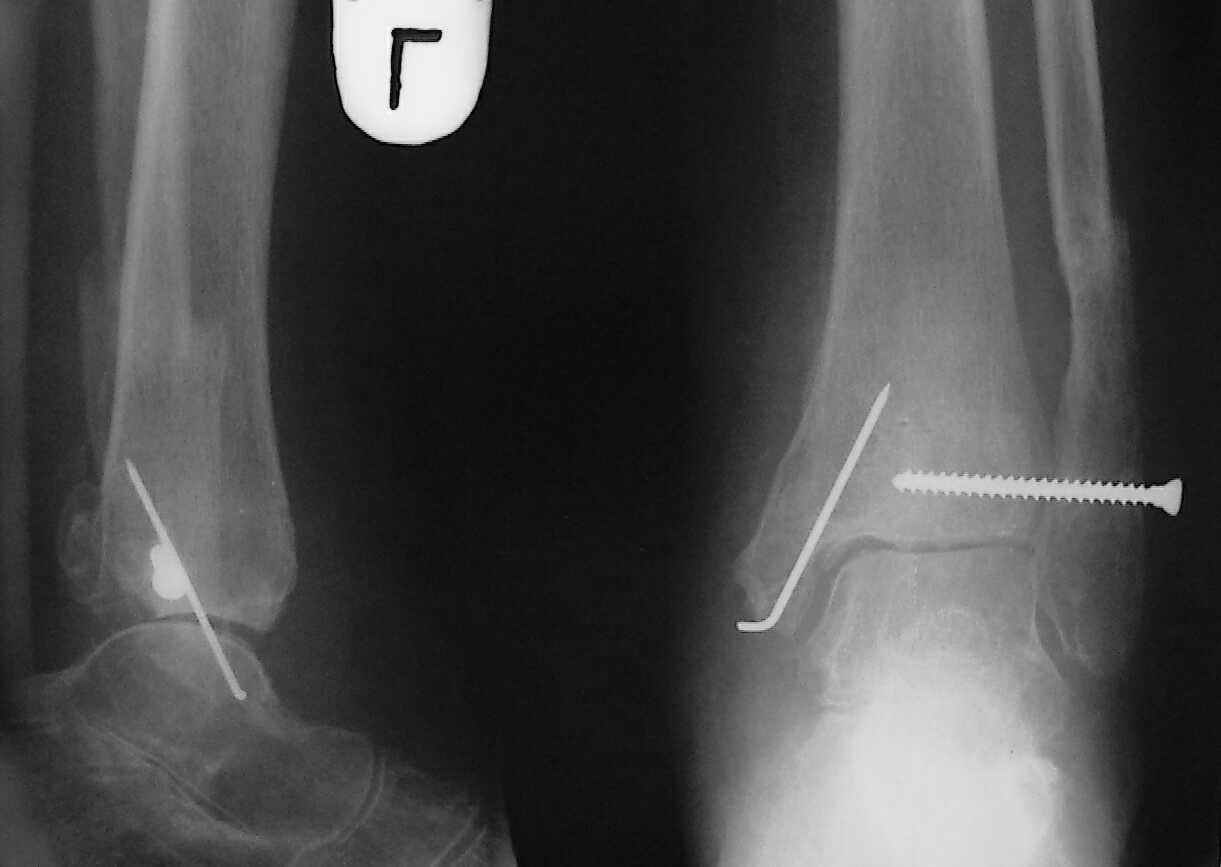

При поступлении - закрытая репозиция, повторная в связи с большим отеком через неделю, подготовлена к остеосинтезу в первых числах декабря. Заживление без осложнений. Циркулярный гипс - 7 недель, снят,часть спиц удалено 20 февраля т.к.пальпировались под кожей, постепенная нагрузка, проблем нет до середины апреля когда появильсь боли с мед. стороны сустава и локалная гиперемия ( трактовалась как флеботромбоз). Повторное поступление 15 апреля - усиление болей,пов. температура, локально выраженная гиперемия.Локально выделений нет. На RTG - деструкция в области мед лодыжки и заднего края. Сахар крови умеренно повышен. Как трактовать проблему, какой диагноз и тактика лечения? Заранее спасибо, Владимир.

Я бы проблему трактовал как изначально нестабильный и нефункциональный остеосинтез с длительной иммобилизацией у больной с сахарным диабетом, ангиопатией и остеопорозом.

Диагноз я бы поставил: неправильно срастающийся перелом обеих лодыжек и заднего края ББК. Ложный сустав мед. лодыжки? Хронический вялотекущий остеоимиелит голеностопа. Сопутствующий - СД, диабетическая ангиопатия 2.

А почему изначально не сделали хоть по Веберу? В чём смысл 6-ти скусанных спиц? И для чего ввинтили несоответствующий методике шуруп в нижнюю треть остеопорозной, практически отсутствующей лодыжки?

Ретроспективно, на Ваш взгляд, что изменилось бы при остеосинтезе более массивными имплантами?(выбор в пользу спиц как раз и был из-за минимального объема оставляемых имплантов) Иммобилизация 7 недель это очень длительно? Результат на 4 RTG - в чем нефункциональность? - согласен, что репозиция заднего края не была достигнута. Какие признаки ложного сустава мед. лодыжки ?

Уважаемый Владимир. Нестабильность и нефункциональность, как мне видится по снимочкам, была изначально,об этом ниже В чём вы видите массивность третьтрубчатой, например титановой 1.5 мм пластины? Ими оперируют во всём мире и получают хорошие результаты, а почему у нас это массивно мне непонятно.Спицевая "тюрьма" хороший способ, но только для временной интраоперационной фиксации, хотя лично я редко пользуюсь, на то есть костодержатели для малых фрагментов и репонирующие винты. Кстати в данном случае, при её остеопорозе лучше было бы поставить LCP (опуская финансовую сторону вопроса, в теории). А вот функциональность - при правильном подборе и установке металлоконструкций пациент нуждается в иммобилизации на срок заживления швов, а уж потом ходьба без нагрузки на оперированную конечность 6 недель - (базовый курс АО). Ретроспективно, как мне видится, при хорошей репозиции и фиксации всё бы консолидировалось, хотя на всё воля божья, но по крайней мере не нужно было бы удалять железки. Иногда ставишь всё как мама родила, а потом очень плохие последствия. Признаки ложного (?) я вижу на снимках,хотя это может быть и банальное отсутствие консолидации за столь длительный срок, что само по себе я бы расценил как ложный сустав. А что Вы сами думаете по этому поводу? И как планируете артродезировать? (если планируете). Мне кажется, самое обидное то, что и эндопротез голеностопного поставить там просто некуда. Я бы думал об очень сомнительном прогнозе.